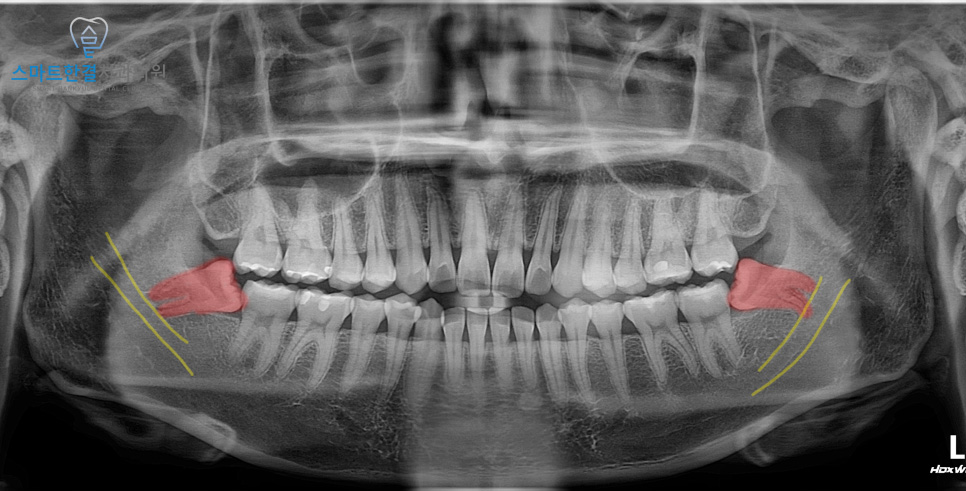

환자분께서는 양쪽 사랑니가

옆으로 비스듬히 누워 자라 있는 상태로,

음식물이 잘 끼고 피곤할 때마다

잇몸이 붓고 불편함을 느껴

본원에 내원해 주셨어요.

머리 일부가 잇몸 밖으로 노출되어 있었고,

관리가 어려워 플라그와

음식물이 끼어 있는 상태였으며

잇몸에 염증이 있는 상황이었는데요.

양쪽 사랑니 모두

비스듬히 누워 있었기 때문에

치아를 분할한 뒤 발치를 진행했어요.

오른쪽은 비교적 무리 없이

발치가 가능했지만,

왼쪽 사랑니는 뿌리가 휘어져 있어

치료 과정에서 뿌리가 부러질 가능성이 높아

더욱 세심한 접근이 필요했어요.